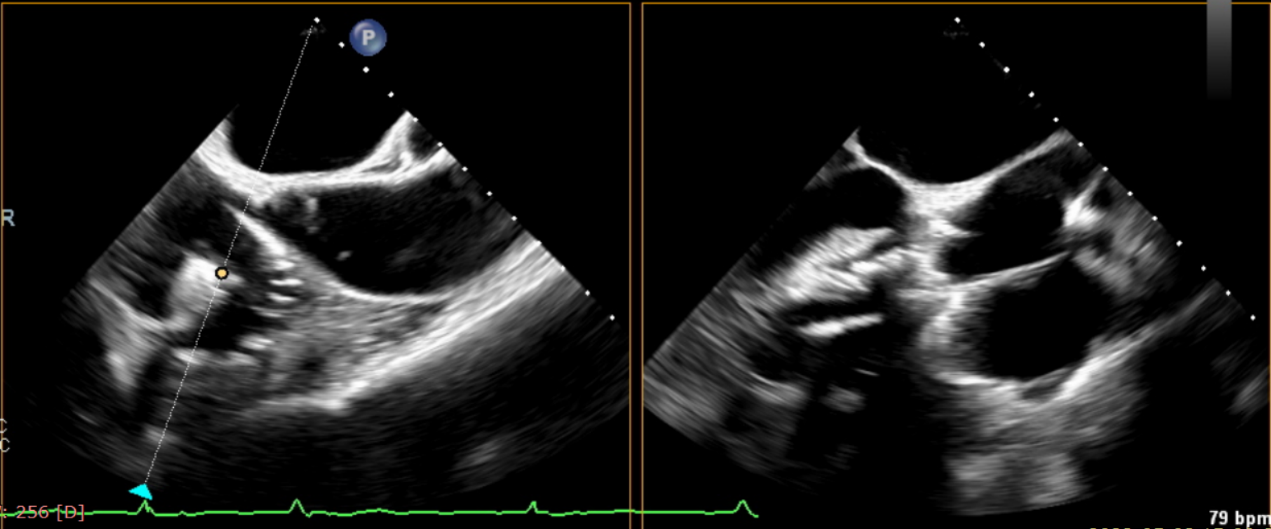

術前超聲提示大量三尖瓣反流

術中輸送器在超聲引導下調整位置

術后超聲提示僅殘余輕微瓣周漏